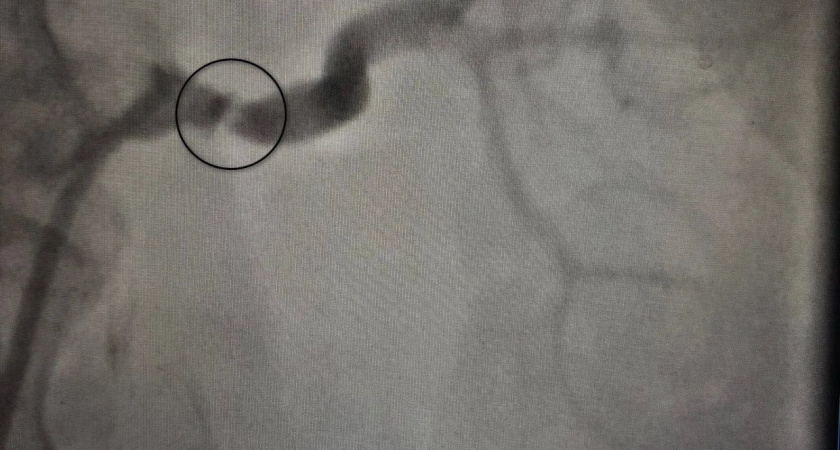

Благодаря новейшим медицинским технологиям и профессионализму местных врачей проблема вскоре была раскрыта. Медики решили применить современную процедуру компьютерной томографической ангиографии, позволяющую детально исследовать внутренние органы и кровеносные сосуды. Проведённое обследование показало сильнейшее сужение главной почечной артерии. Это и являлось источником повышенного давления.

Именно благодаря этому открытию возникла уникальная возможность решить проблему кардинально. Руководствуясь выводами обследования, специалисты приняли решение провести малотравматичную эндоваскулярную операцию. Стентом был устранён дефект сосуда, нормализовав кровообращение в почке.